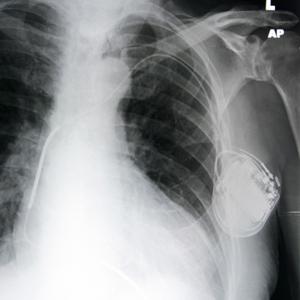

X-ray showing a pacemaker

FAITH LAPIDUS: A pacemaker is a small device that doctors place in people with an abnormal heartbeat. If a heart beats too slowly, the device will use electrical signals to help set a normal rate. Some pacemakers include a defibrillator, which gives a shock if the heart beats too fast.

Pacemakers may be permanent or temporary. But one thing is sure. Developing countries need more of them as more people get heart disease.

A big problem, however, is cost. Buying and implanting a pacemaker costs from 5,000 to 15,000 dollars. Yet doctors at the University of Michigan think they know a way to lower that cost. The idea is to reuse pacemakers.